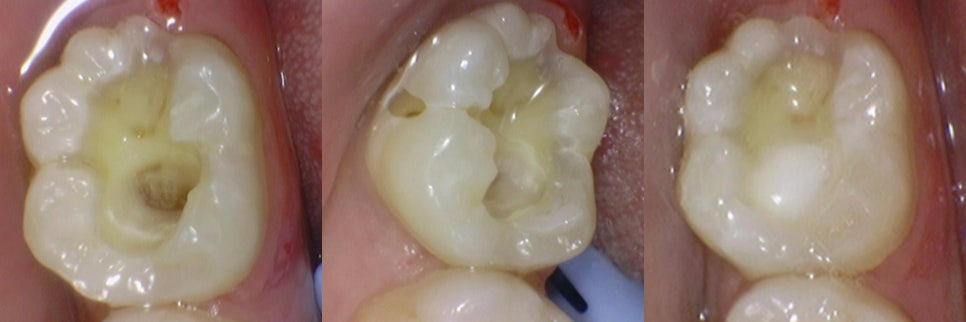

나머지 어금니 또한 충치를 걷어내고

인레이 와동을 형성한 모습입니다.

인레이 제작 과정에서도 전체적인

치아의 색상, 교합, 인접치아의

연관성을 고려해야 됩니다.

구강 맨 안쪽에 위치하여

칫솔이 제대로 닿기 어려운 부위인

어금니의 경우에는 좀 더 깊은 충치가 확인됩니다.

이때는 충치를 제거한 후 레진으로 보강하여 크라운을 씌워 마무리하면 됩니다.